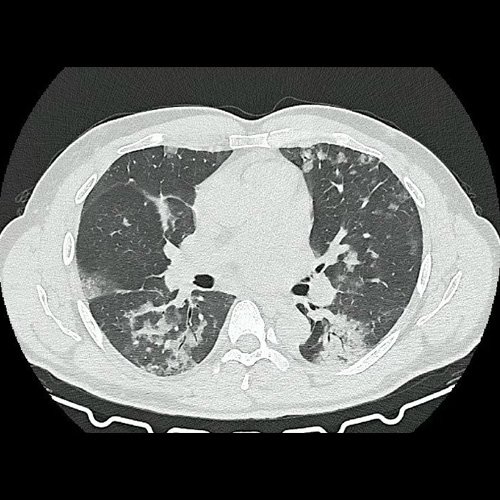

- Tomografía de tórax sin contraste endovenoso (Dia 0):Se observan múltiples áreas de consolidación parenquimatosa con broncograma aéreo y de distribución difusa por ambos pulmones, predominando en los lóbulos inferiores, asociadas a engrosamiento de los septos y rodeadas de tenue vidrio esmerilado. Se identifican estructuras ganglionares lateroaórticas, pretraqueales y subcarinales, ninguna de ellas sin alcanzar rango megálico.

Tomografia de torax sin contraste endovenosos (Ventana pulmonar-corte axial)

Tomografia de torax sin contraste endovenosos (Ventana pulmonar-corte axial)

Tomografia de torax sin contraste endovenosos (Ventana pulmonar-corte axial)